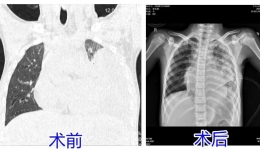

发热咳嗽8天,孩子肺差点“废了”!这些信号别忽视